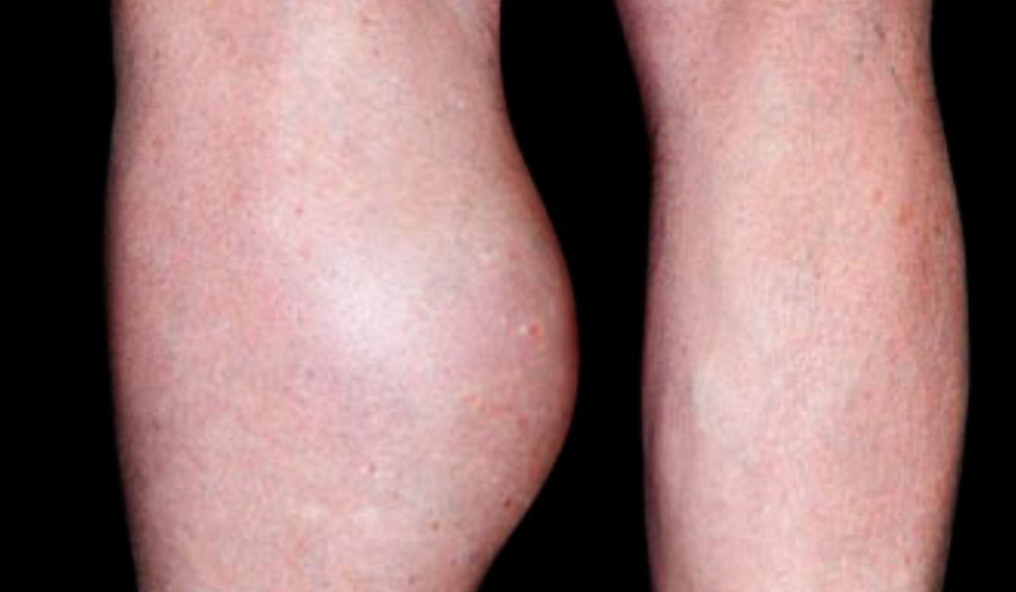

What is the likely diagnosis?

a. DVT -

Name 2 differential diagnosis?

a. Hematoma

b. Ruptured backer cyst -

What 2 steps are advised to confirm diagnosis?

a. Doppler UltraSound

b. D dimer test